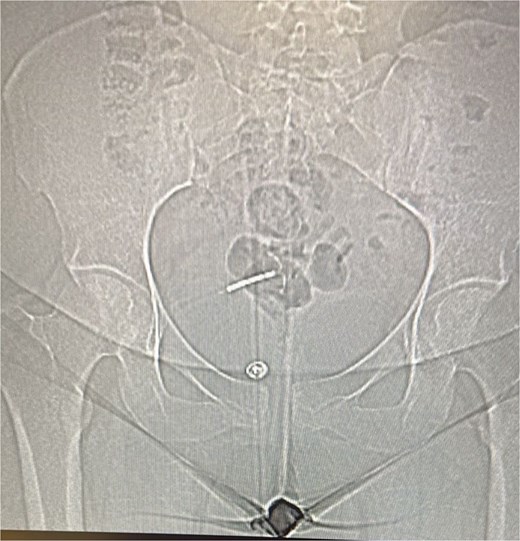

Given persistent symptoms and inconclusive plain radiography, an abdominopelvic computed tomography (CT) scan was performed, revealing the IUD embedded in the anterior abdominal wall with an associated loculated fluid collection suggestive of a localized abscess (Fig. 2).

(a–c) The CT scan revealed the IUD embedded between the anterior abdominal wall and urinary bladder with a small, localized fluid collection suggestive of an abscess.